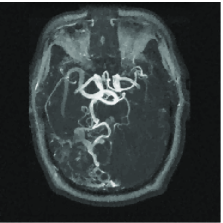

We mimic an MR experiment by taking our unknown image to be the pixel MR angiogram image shown in Figure 12(a). We sample the image along 80 lines in the Fourier domain (see Figure 12(b)), effectively taking real-valued measurements . In plain terms, we undersample by a factor of about 3.

Figure 12(c) shows the minimum energy reconstruction which solves

| (18) |

Figure 12(d) shows the result of TV minimization. The minimum -analysis (17) solution where is a three-scale redundant D4 wavelet dictionary that is times overcomplete, is shown on Figure 12(e). Figure 12(f) shows the result of reweighting the analysis with and set to 100. For a point of comparison, the maximum wavelet coefficient has amplitude 4020, and approximately 108000 coefficients (out of 655360) have amplitude greater than 100.

We can reinterpret these results by comparing the reconstruction quality to the best -term approximation to the image in a nonredundant wavelet dictionary. For example, an reconstruction error equivalent to the reconstruction of Figure 12(c) would require keeping the largest wavelet coefficients from the orthogonal wavelet transform of our test image. In this sense, the requisite oversampling factor can be thought of as being . Of course this can be substantially improved by encouraging sparsity, and the factor is reduced to using TV minimization, to using analysis, and to using reweighted analysis.

We would like to be clear about what this means. Consider the image in Figure 12(a) and its best -term wavelet approximation with ; that is, the approximation obtained by computing all the D4 wavelet coefficients and retaining the largest in the expansion of the object (and throwing out the others). Then we have shown that the image obtained by measuring real-valued Fourier measurements and solving the iterative reweighted analysis has just about the same accuracy. That is, the oversampling factor needed to obtain an image of the same quality as if one knew ahead of time the locations of the most significant pieces of information and their value, is just 3.